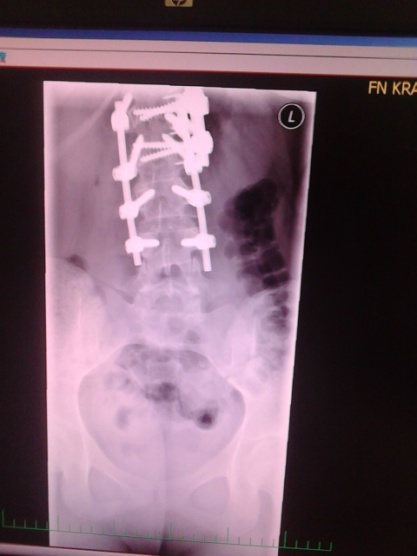

Ahoj, jsem po téhle operaci už17 let. Od druhého po předposlední obratel mám kovový aparát, záda neohnu prakticky vůbec. Upřímně, kdybych byla svůj rodič v té době, tak bych sama sebe na tu operaci nikdy nepustila. Jenže naši nehlídali jestli cvičím a já puber´ták na to kašlala a korzet odkládala. Záda mě bolí prakticky pořád, mám je ztuhlé a občas mám dokonce pocit, že tu tyčku cítím. Posledních několik let cvičím hodně jogu, pilates, posiluju svaly, což dost pomáhá, přestože jsem v polohách co můžu dost omezená. Ale je to dlouho, určitě mají jiné metody. Držím pěsti!

Zdravím jak jsem psala že mám jet v lednu do Prahy na kontrolu jestli jdu nebo nejdu na operaci tak mi doktor oznámil že půjdu tetka na operaci nebo za dva roky a to je možnost že už to nebude operativní. Takže jsem se rozhodla ji podstoupit tetka. Jsem 14 dní po operaci. Týden jsem ležela v nemocnici a nebyl to zákrok jako ty dva minule. Musím akorát nosit berle protože mi operoval bederní páteř. Tetka už bych na žádnou operaci neměla jít a an tam není co už operovat.